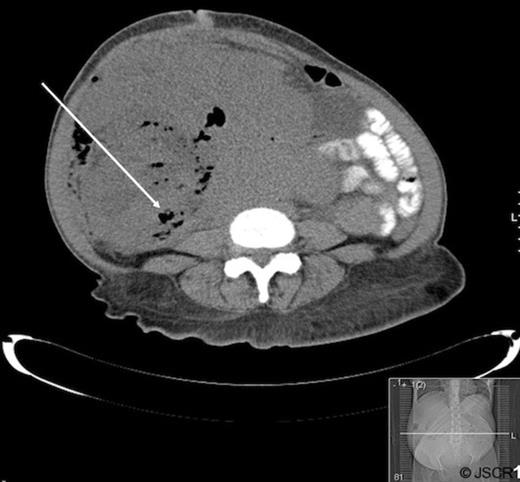

Patient A is a 67 year old female with a history of pelvic leiomyosarcoma and total abdominal hysterectomy with bilateral salpingo-oopherectomy who presented with abdominal discomfort, early satiety and weight loss. On physical exam she was noted to have a large, firm abdominal mass. Admission labs revealed a marked leukocytosis (WBC=45 700) and blood cultures positive for E. coli. CT of the abdomen and pelvis revealed a mass occupying the pelvis and majority of the abdomen with air pockets, questionable portal venous gas and mild left hydronephrosis (Figure 1).

Abdominal and pelvic CT of patient A demonstrating a large mass with air pockets (arrow).

The patient was treated with antibiotic therapy and underwent surgical resection of a 40 cm retroperitoneal and pelvic sarcoma. During the operation the right colon was noted to have perforated into the tumor, with succus entericus grossly visible. Surgical approach was broadened to include a right hemicolectomy, sigmoidectomy with colostomy and segmental small bowel resection. Pathological analysis revealed a malignant spindle cell tumor with negative immunohistochemical staining for CD117 and CD10 and mild reactivity for desmin and muscle specific actin, making low grade leiomyosarcoma the most likely diagnosis.